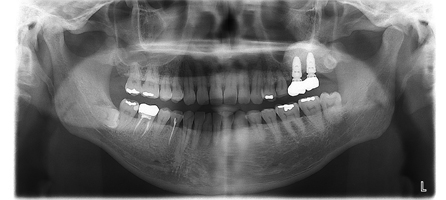

治療前レントゲン

治療後レントゲン